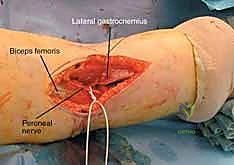

The lateral side harbors the common peroneal nerve, a structure of paramount concern. The nerve courses distally from the popliteal fossa, wrapping tightly around the fibular neck before diving into the anterior and lateral compartments of the leg. It is highly vulnerable to traction injuries during severe varus trauma and is at significant iatrogenic risk during extensive lateral dissection, retractor placement, or the application of lateral plates that extend distally. The nerve provides motor innervation for ankle dorsiflexion and foot eversion; an injury here results in a devastating foot drop. Preoperative, intraoperative, and postoperative assessment of peroneal nerve function is an absolute medicolegal and clinical imperative.